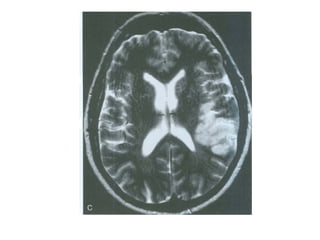

• On T2WI and FLAIR infarction is seen as

high SI.

These sequences detect 80% of

infarctions before 24 hours.

They may be negative up to 2-4 hours

post-ictus!

• High signal on conventional MR-

sequences is comparable to hypodensity

on CT.

It is the result of irreversible injury with cell

death.

So hyperintensity means BAD news: dead

brain.